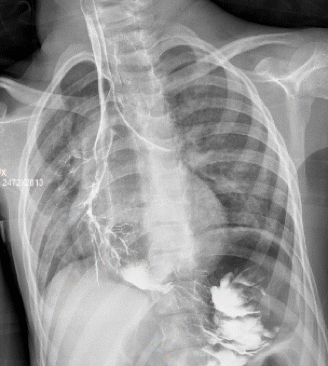

Capito (per caso) in stanza al momento del pasto, che viene somministrato dalla mamma a ragazzo semisdraiato con necessità di somministrare almeno 2-3 cucchiaini di cibo frullato prima di innescare un riflesso deglutitorio, con comparsa di tosse e distonia dei muscoli facciali a ogni boccone. La mamma mi dice che a casa in ambiente familiare Thomas mangia meglio e che forse in questi giorni è disturbato dal raffreddore… se ha più tosse è per via del virus e non crede che mangiando “gli vada per storto”. Il giorno seguente viene eseguito un transito con pasto baritato (Figura 1)

Figura 1. RX transito con budino baritato.

Thomas è stato dimesso dopo posizionamento urgente di PEG (vedendo l’immagine anche la mamma si è convinta), in terapia con ferro e vitamina D (che non assumeva!).